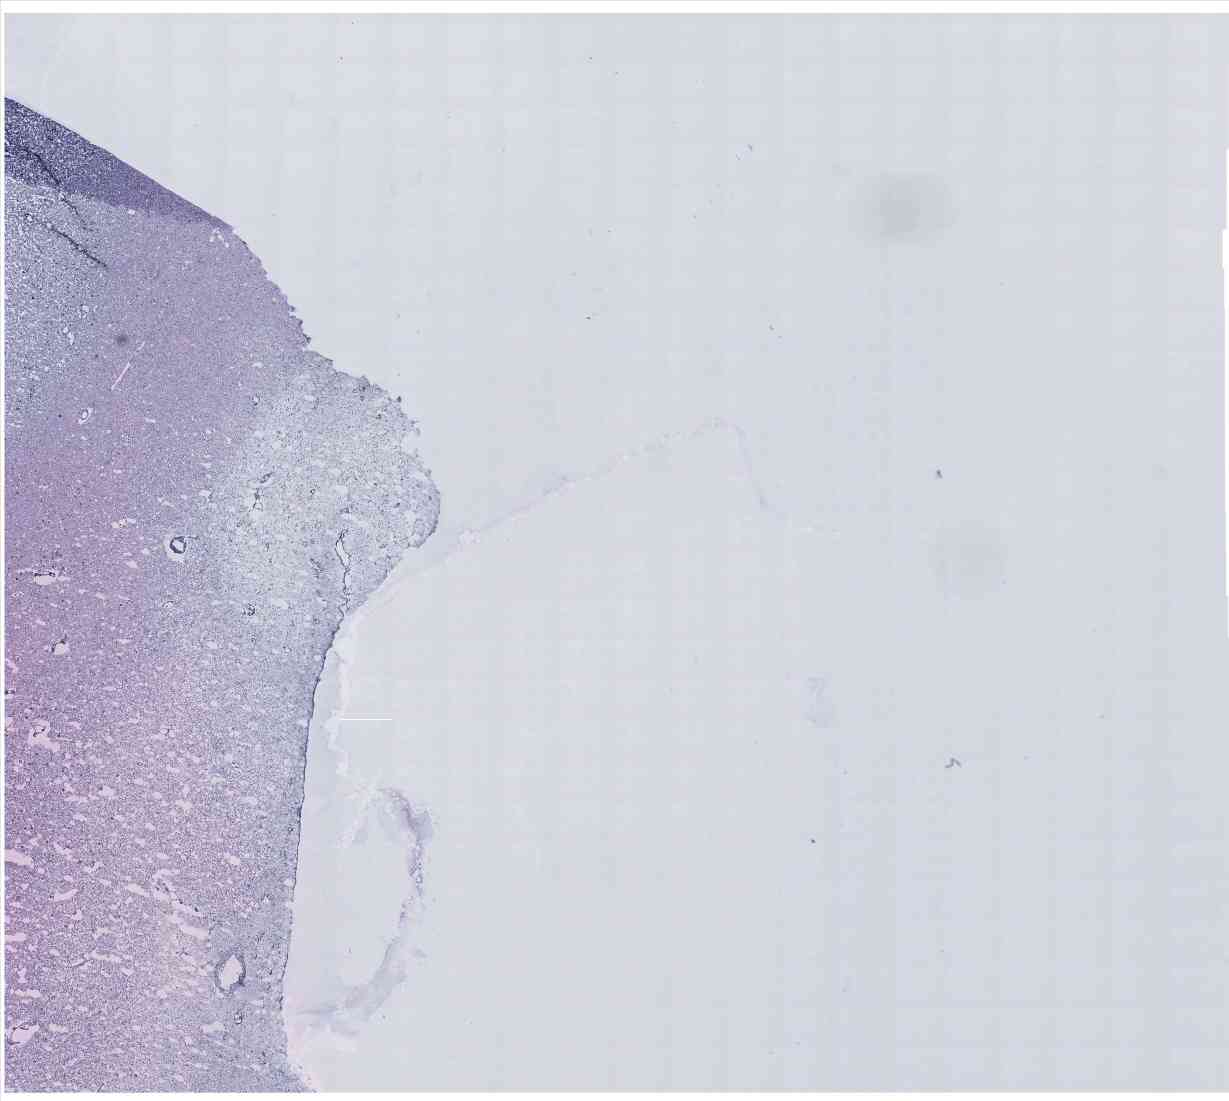

Chip 022 Well C2